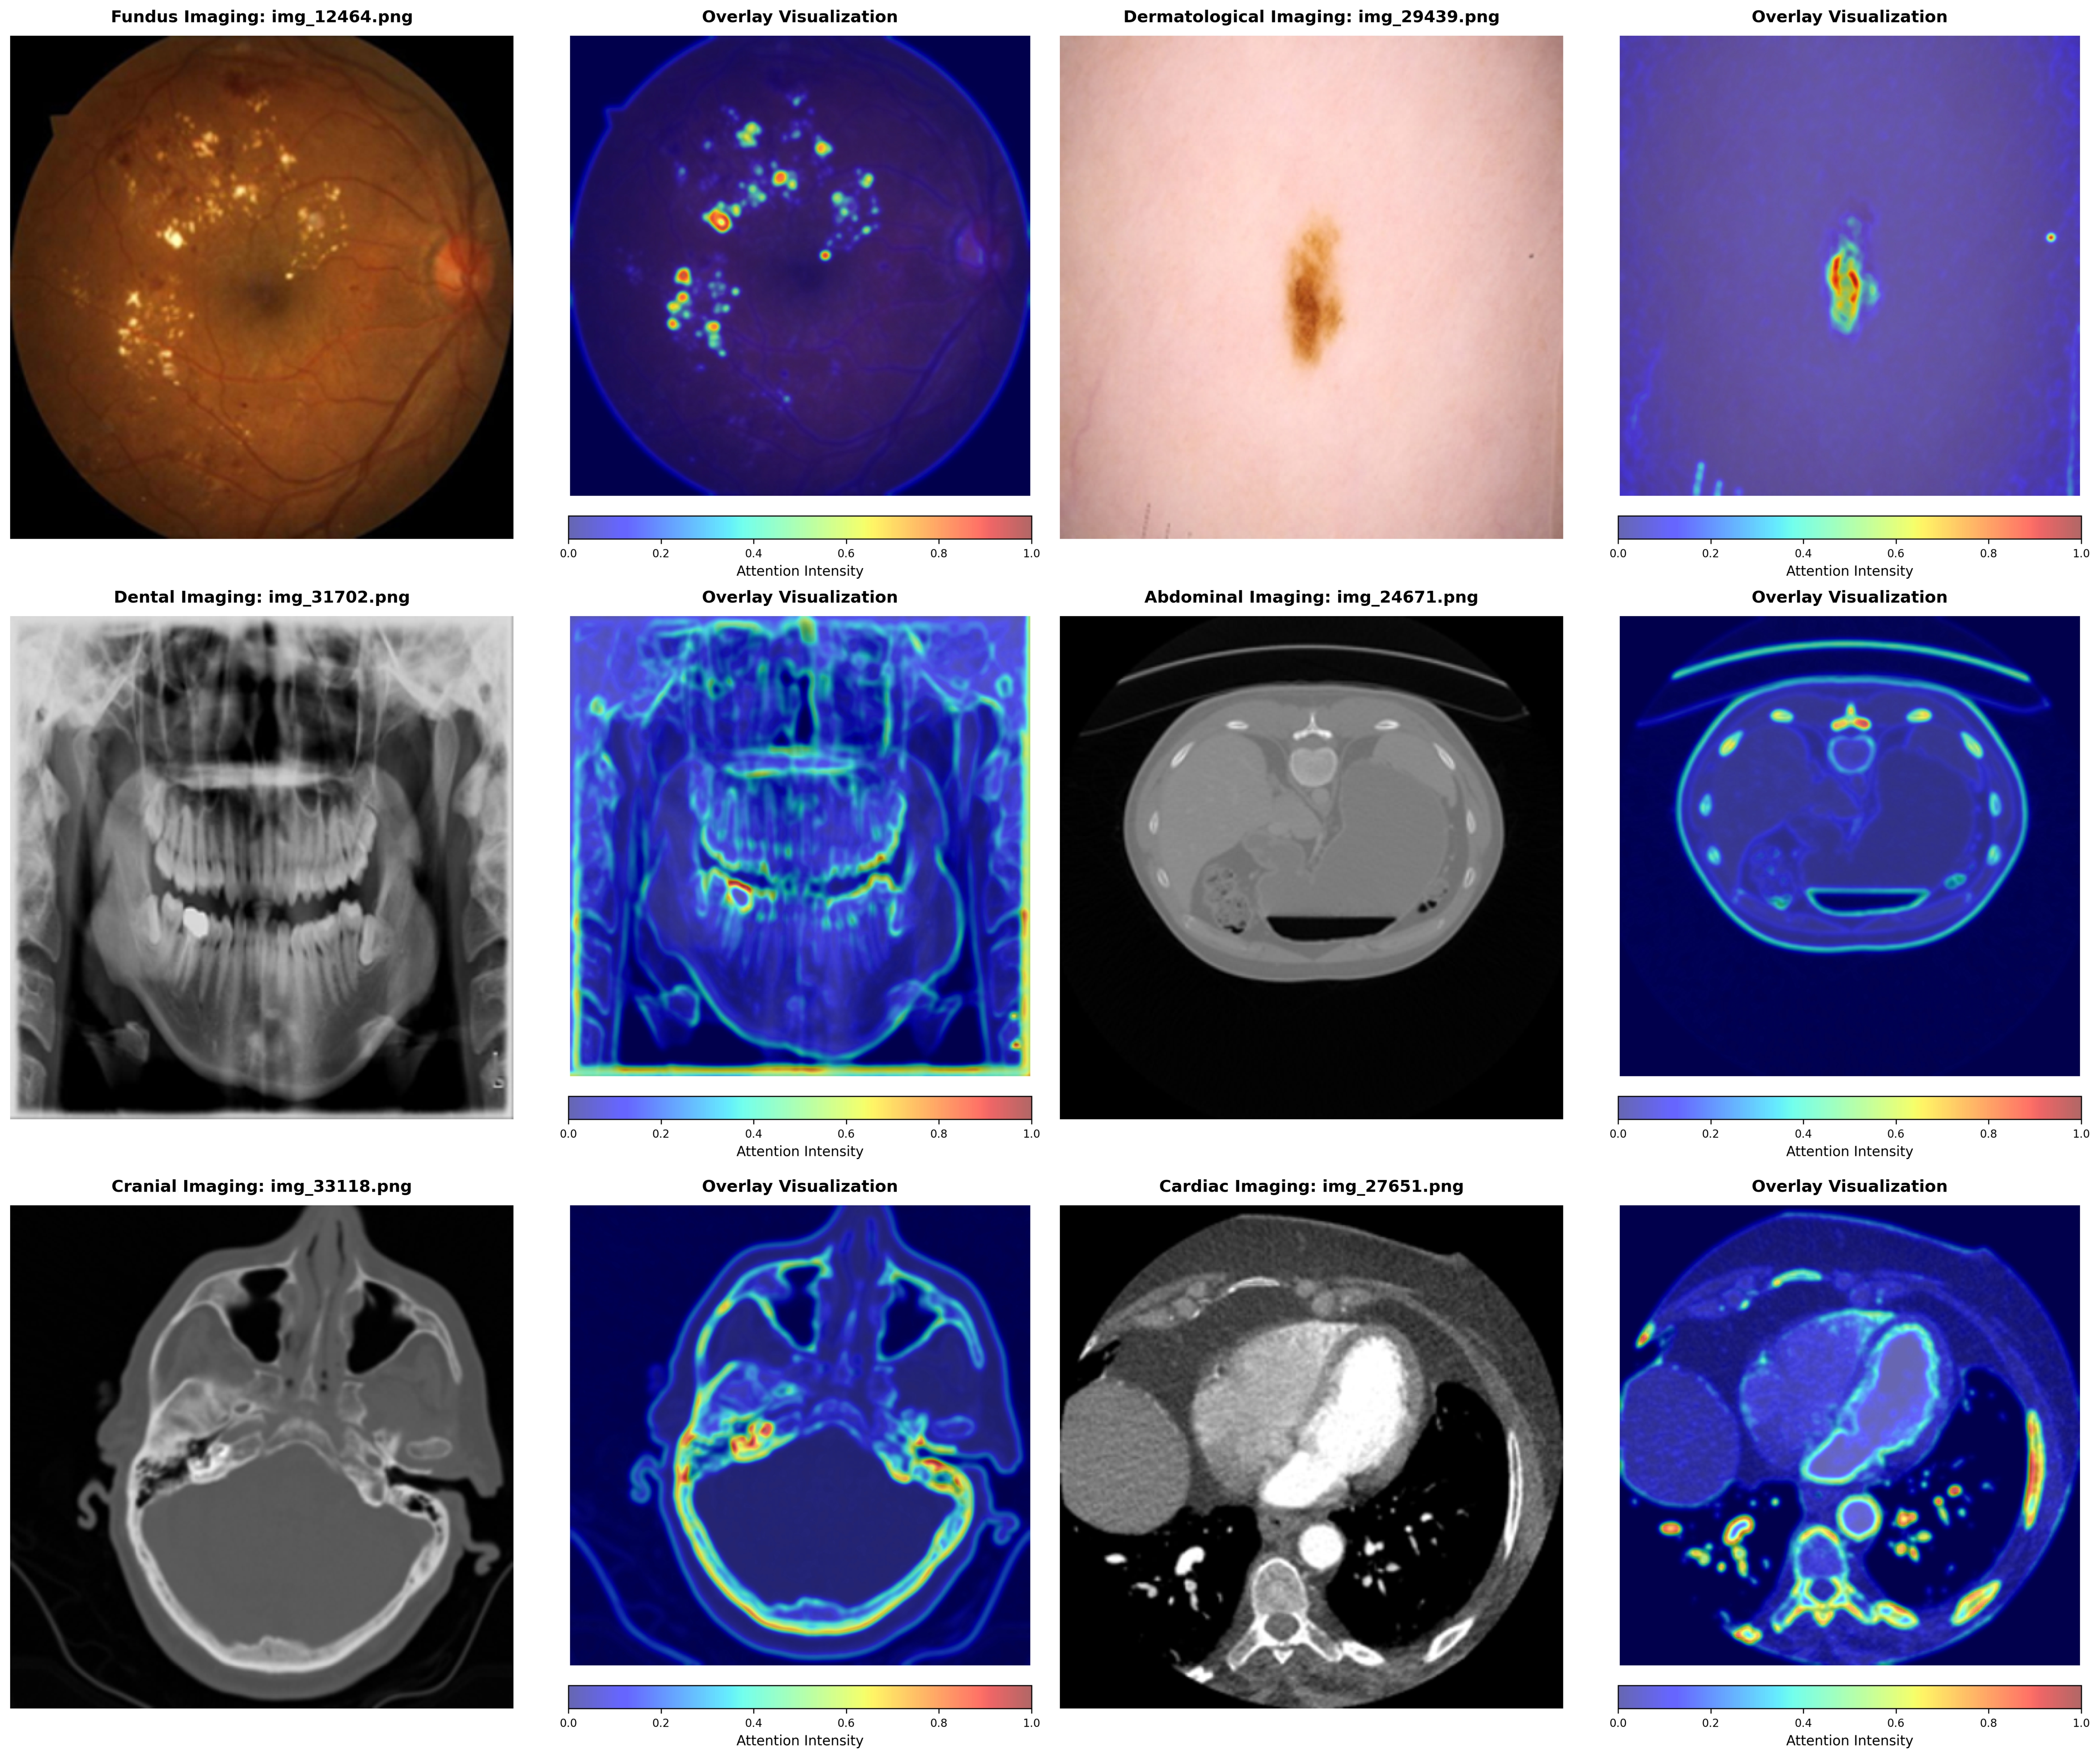

Appendix E E. Attention Visualization

Refer to caption

Figure 7: Attention visualization across different medical imaging modalities. Left columns show original images, right columns display attention heatmaps. RegionMed-CLIP successfully localizes pathologically relevant regions across diverse modalities.